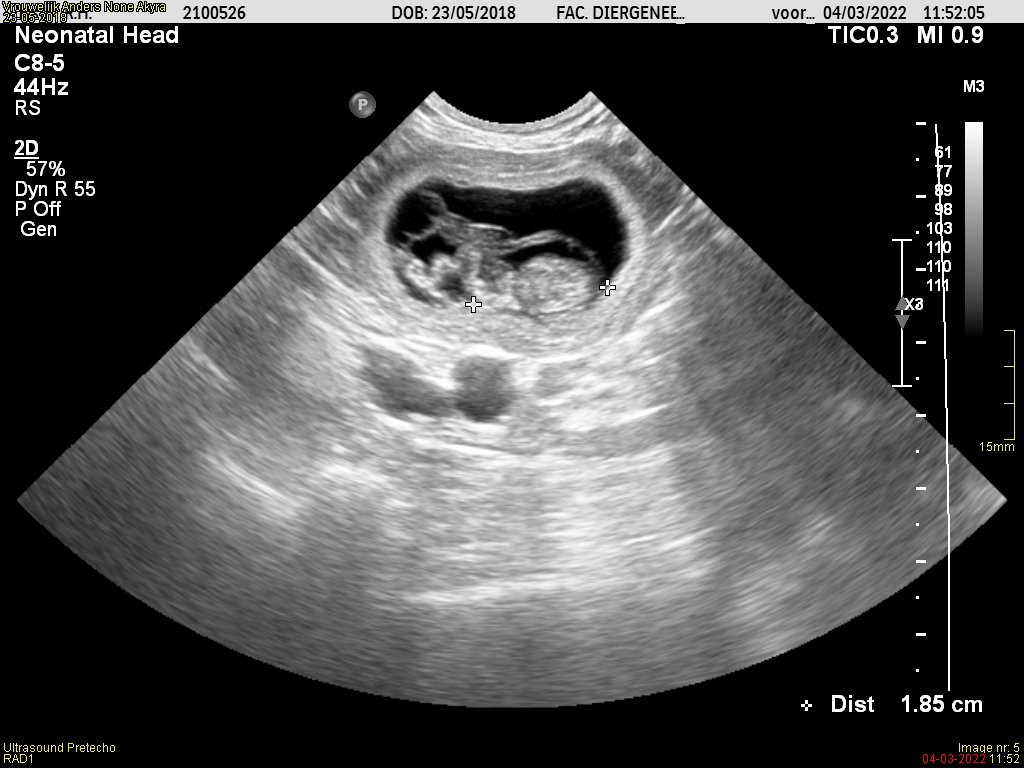

Vandaag een drachtecho gehad van Akyra.

Het mag duidelijk zijn dat Akyra drachtig is! We verwachten de pups begin April.